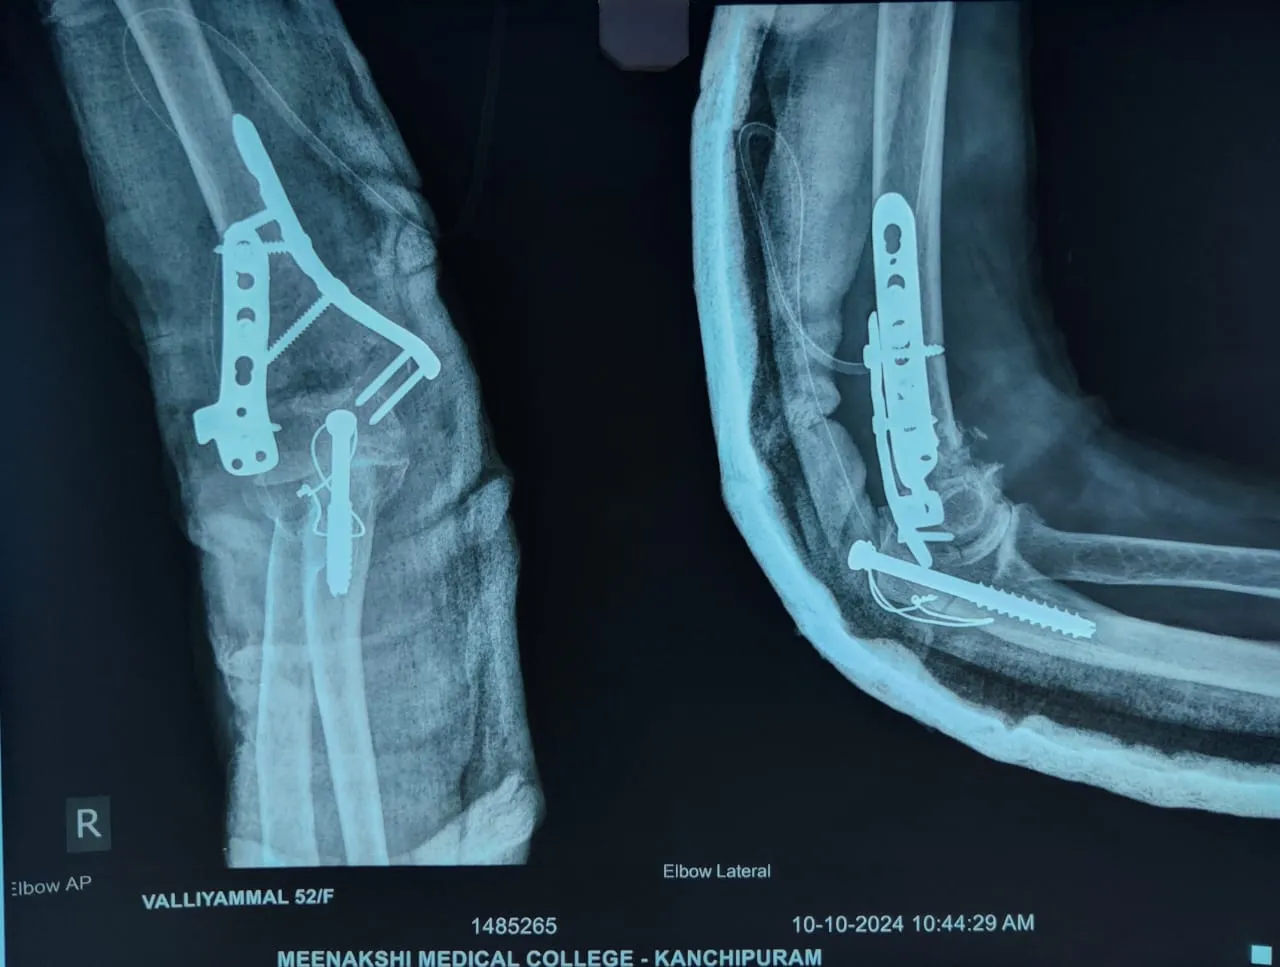

Quality and affordable healthcare has long been the essence in the field of medical sciences & treatment. Every patient expects an early diagnosis and a planned approach to treatment procedures with affordability and access to quality healthcare. Knee replacement, Hip replacement, Fracture treatment are being done by Dr.P.Sankaralingam at very affordable costs without compromising on quality.

Dr.P.Sankaralingam M.S(ortho)., DNB (ortho).,MNAMS is an experienced senior consultant Orthopaedic surgeon who does about 350 joint replacement surgeries per year in addition to treatment of Trauma cases.

Standard Hospital, Chennai’s Centre of Excellence for Orthopaedics offers minimally invasive surgeries for faster recovery.